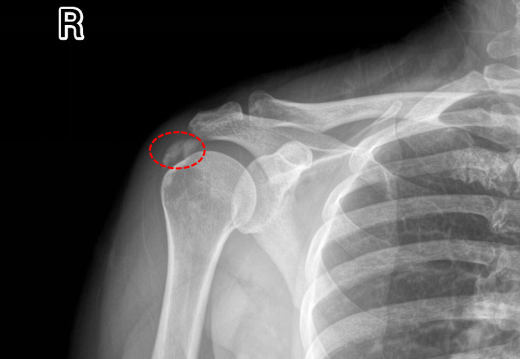

近日,年近六旬的黄阿姨无明显诱因下骤发右侧肩痛两天,夜间痛到无法入睡,止痛药仅可缓解三四小时,又再发持续剧痛,而且伴有右肩活动障碍,稍微活动一下右肩,愈加钻心疼痛来袭。饱受折磨的黄阿姨到桂林医科大学第二附属医院运动医学科门诊就诊,副主任医师谢小军一听病史,初步怀疑钙化性肌腱炎,通过初步拍X线,果真病因是它。

这种疾病名为肩关节钙化性肌腱炎,肩关节钙化性肌腱炎是肩部肌腱内钙盐异常沉积引发的炎症性疾病,常见于40-50岁人群,以肩部剧烈疼痛、活动受限为主要表现。钙化性肌腱炎是肌腱组织内出现羟基磷灰石晶体沉积的病理状态,肩袖肌腱(尤其是冈上肌腱)最常受累。钙盐沉积可能与肌腱局部缺氧、代谢异常或退行性变有关,导致炎症反应和机械性刺激,引发疼痛和活动障碍。急性期疼痛剧烈,夜间加重,可能放射至上臂;抬手、外展或旋转动作困难,严重时影响穿衣、梳头等日常活动。肩峰下或肱骨大结节处压痛,部分患者伴局部肿胀。若钙化灶>1.5cm,往往需关节镜手术治疗。

门诊医生立即为黄阿姨办理了住院,并于当天晚上完成急诊手术,通过3个0.5cm小切口在关节镜下解决了病因。镜下可见冈上肌腱内冒出牙膏状钙化沉积物,彻底清理后缝合肩袖破口。